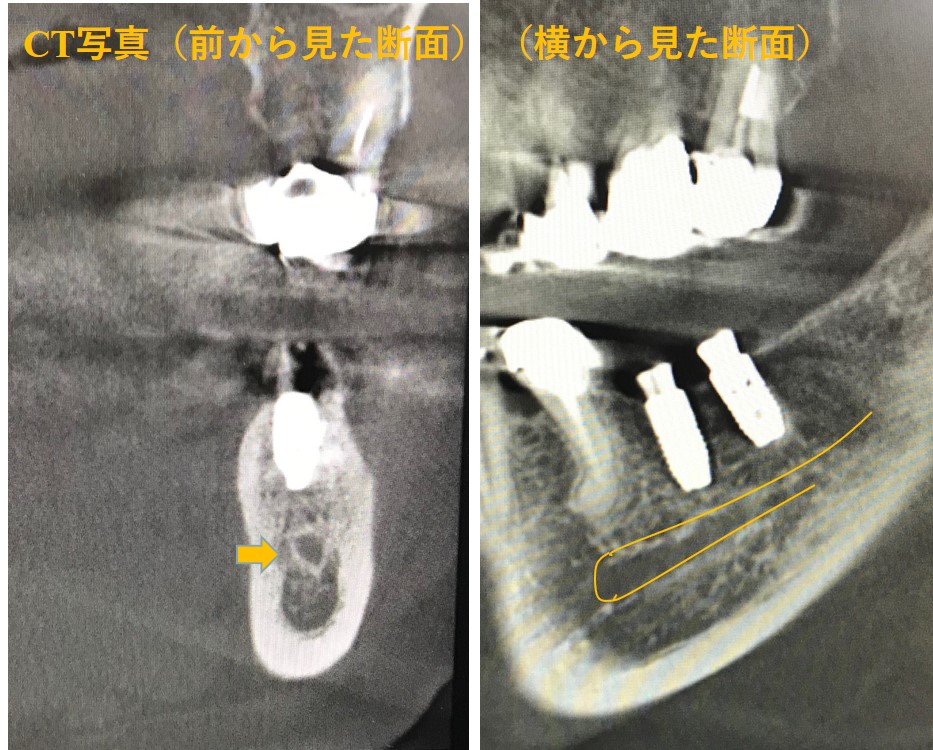

CT撮影の「横から見た面」では④と⑤ともに黒い影が見えます。CT撮影の「上から見た面」では、④の周りに黒い影が大きく見えます。

さらに、「前から見た面」で詳しく見てみましょう。④の歯根の周りの骨が吸収して無くなっています。⑤の歯根の周りの骨も少し吸収して骨が溶けていますが、これを見てもわかるようにこの「膿の袋」の原因歯は④であったことがわかりました。